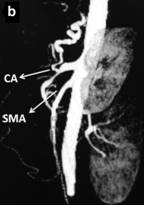

Ultrasonography of the abdomen revealed a hypoechoic 30x40 mm mass in the pancreatic body. Abdominal CT scan confirmed a solid heterogeneous mass of the pancreatic body, without cystic component. No radiologic signs of metastasis were found (Figure 1). Vascular reconstruction of CT scan showed a suspicious infiltration of the common hepatic and the splenic arteries with a total occlusion of the celiac trunk with a normal flow thought the gastro-duodenal artery. Furthermore, multiples atheromatous plaques with calcification were seen in the aorta. Similar findings were found in the pancreatic magnetic resonance. In the endosonographic study, the mass presents a high vascularization, confirming the infiltration of the major arteries at the origin of the celiac trunk. In the same study a biopsy was performed, compatible with adenocarcinoma.

Figure 1. Preoperative CT scan. a. A 4 cm tumor in the body of the pancreas narrowing of the vessels at the origin of the celiac axis due to tumor encasement. b. Superior mesenteric artery is not involved. CA: celiac axis; CHA: common hepatic artery; SA: splenic artery; SMA: superior mesenteric artery |